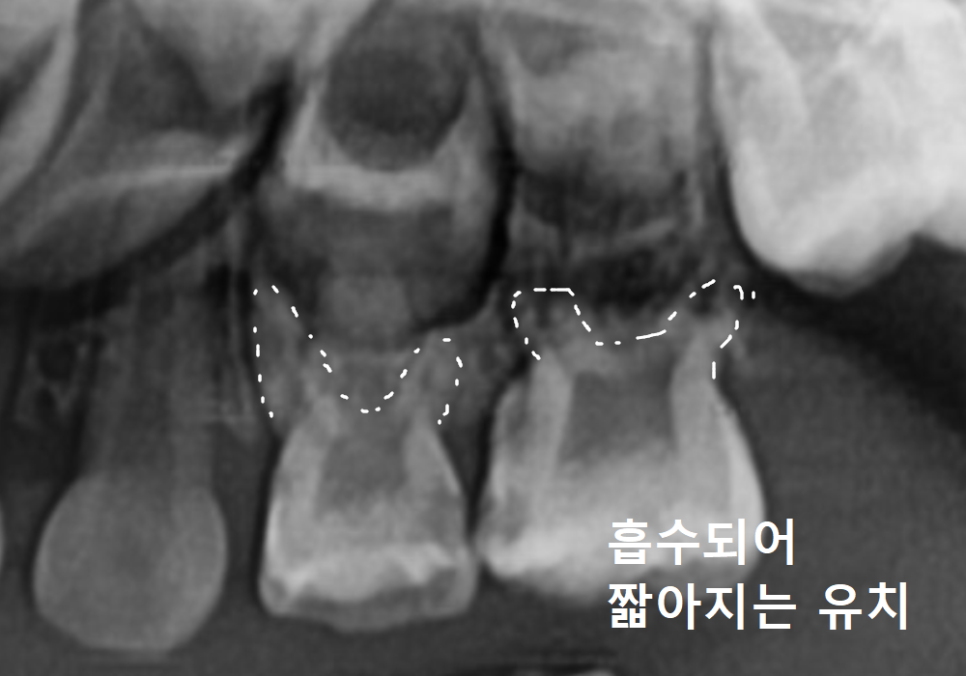

게다가 시간이 흐를수록 뿌리가

스스로 조금씩 흡수되면서

점점 더 짧아지게 되는데,

결국 치아를 지탱하는 힘이 한계에 다다르면

흔들림이 생기고 시큰거리는 통증으로

이어지게 됩니다.

뿌리 끝에 이미 염증이 생겨 있었고,

그 염증 때문에 주변 잇몸뼈가 녹아내려

뿌리 끝자락만 간신히 뼈에 걸쳐져 있는 상태였어요.